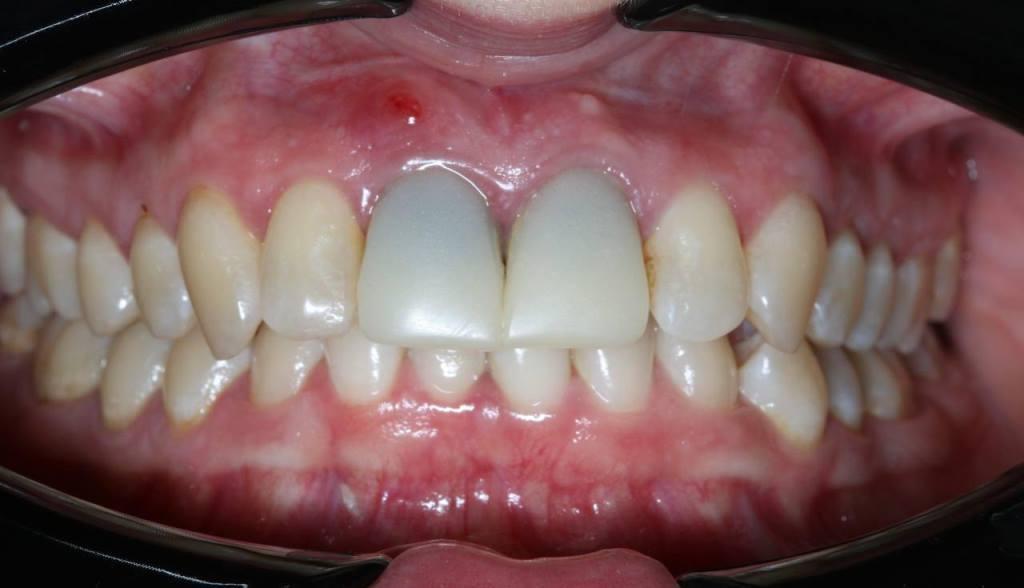

Пациентке около 40 лет. Еще в детстве она упала с велосипеда и повредила два центральных зуба на верхней челюсти.

И вот пациентка, устав от неоднократных визитов к стоматологам по поводу этих зубов, решила попрощаться с ними и установить имплантаты. Но в четырех клиниках, куда она обращалась, ей сообщали, что нужно удалить эти зубы, подождать 2-3 месяца, потом сделать костную пластику, через 6 месяцев установить имплантаты и еще через 6 месяцев сделать коронки. Т.е. все лечение должно занять больше года.

Фото 1.

По рекомендации своего супруга она обратилась в нашу клинику. Действительно, анатомическое расположение зубов таково, что после их удаления образуется большой горизонтальный костный дефект. Будет дефицит костной ткани.